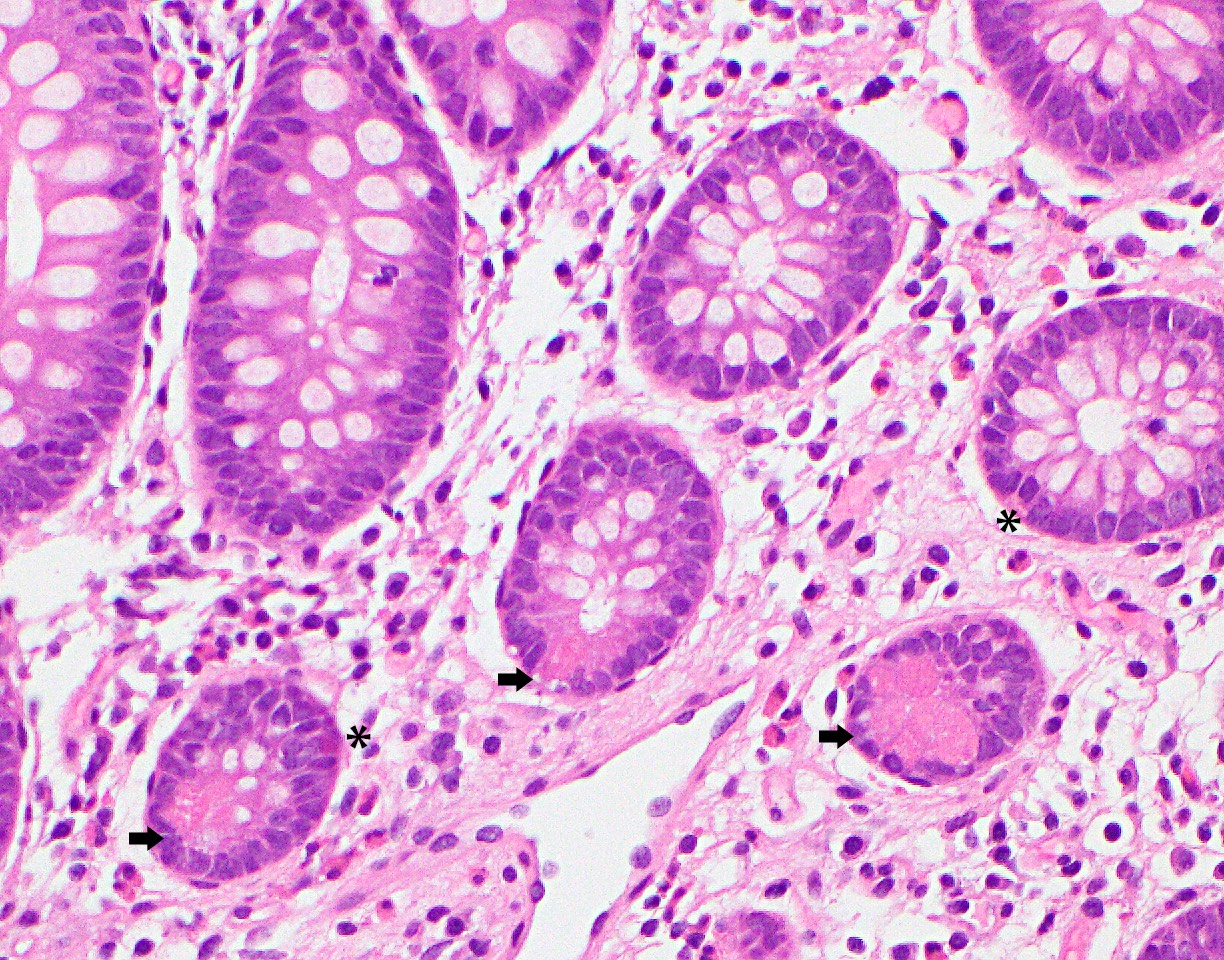

Microscopic (histologic) images

- Other cell types of the epithelium:

- Enteroendocrine cells:

- Located at the base of the crypts and have eosinophilic secretory granules in the cytoplasm with apically located nuclei

- Apical location of the nuclei helps to differentiate these cells from the Paneth cells

- Paneth cells:

- Paneth cells have a triangular shape with densely eosinophilic cytoplasmic granules

- Nuclei are basally located, unlike enteroendocrine cells described above, a distinction important in the left colon, since the presence of Paneth cells in this part of colon is abnormal and could be a sign of chronic injury

D. Paneth cells. They have a triangular shape with densely eosinophilic cytoplasmic granules and basally located nuclei, as opposed to enteroendocrine cells (see image above). Their presence in the left side of the colon can be a sign of inflammatory bowel disease.